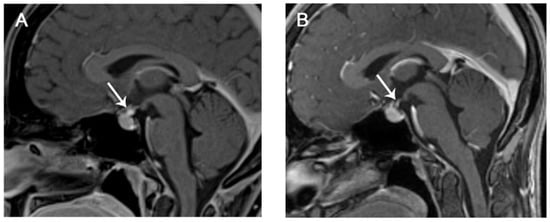

8.3. Diagnosis and Imaging

| Imaging Modality | Findings |

| CT |

| MR Necessary if suspected |

| PET-CT (18F-FDG) |